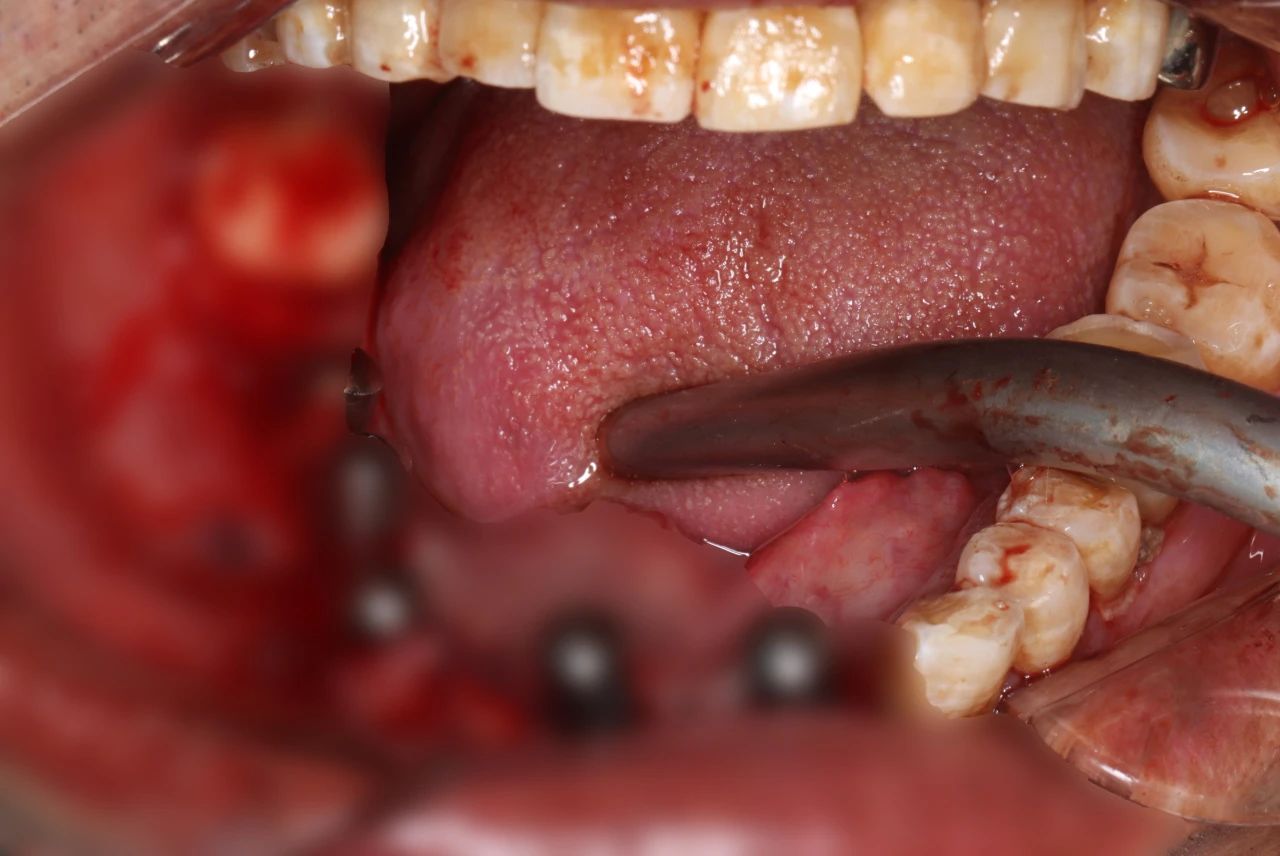

-下颌即刻种植+即刻修复中-

-下颌即刻种植+即刻修复中-